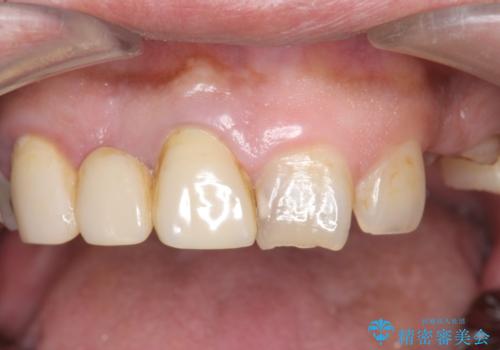

オールセラミッククラウン ブリッジによる欠損歯の補綴

根尖病変が認められる歯は再根管治療を行い、歯根が破折していた左上4は抜歯しました。

インプラントは希望されなかったため、左側は1番から7番のロングスパンブリッジによる補綴を行いました。

今回用いたオールセラミッククラウンは、ジルコニアフレームという白い素材の上にセラミックを盛っているため審美性が非常に高いのが特徴です。

またジルコニアは人工ダイヤモンドの材料にも使われているほど高い強度を持っており、そのためオールセラミッククラウンは審美性だけでなく、奥歯やブリッジの補綴も可能とするクラウンです。